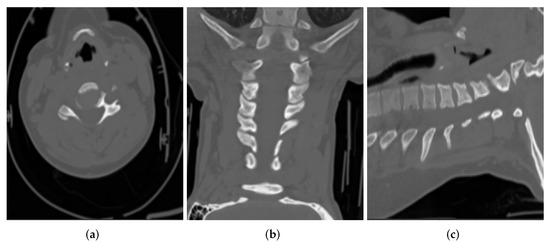

The export process at the source does a first round of de-identification on the DICOM files. These files are then put through a second round of de-identification/post-processing for further validation. As an example of DICOM CT images, de-identified at the source, Figure 2 shows DICOM CT images belonging to a 65 year old female patient, in three main views (i.e., axial, coronal, sagittal):

Figure 2.

Sample CT images from (a) Axial, (b) Coronal and (c) Sagittal views for a patient.